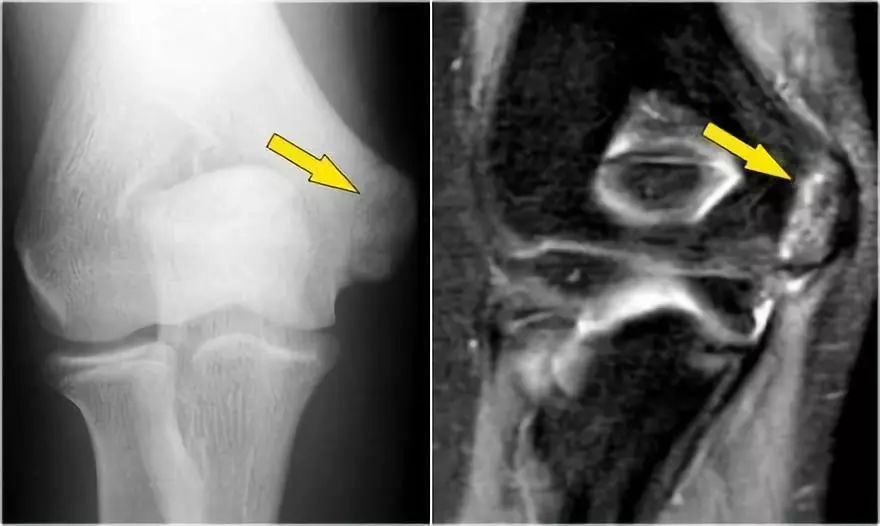

下面的射线照片是一名15岁的棒球运动员,有4年的肘部疼痛史以及最近一次锁定。肱骨小头有一个局部透明度区和一些破碎,这是典型的小头骨软骨病变,

这对于头状骨的是典型的,锁定可能是游离体的结果。

MR-关节造影证实了骨软骨病变。在肱骨和骨软骨病变之间存在钆造影剂,这表明它是不稳定的。注意轴向图像上看到的碎片。